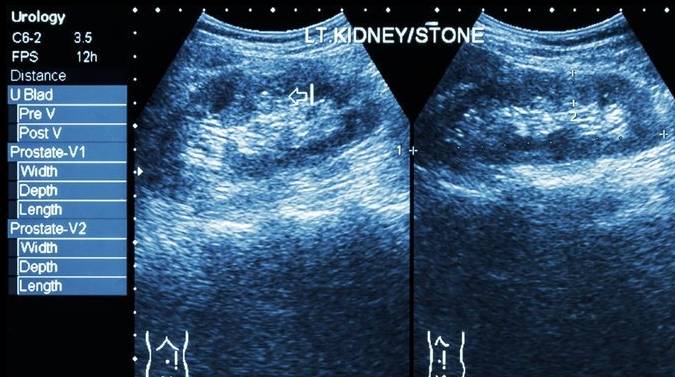

“四年了 , 就在刚刚 , 那颗石头终于离开了我的身体 。 ”年仅25岁的丽霞(化名)缓下了一口气 。

丽霞在高二寄宿的时候 , 由于学校水质问题 , 得了右肾结石 , 并伴随出现积水 。

在医院做完体外碎石 , 安稳度过3年之后 , 当丽霞认为自己已平安度过“难关”的时候 , 肾结石又再一次地来了 , 而且更为猛烈 。

文章图片

所幸的是 , 丽霞及时前往医院进行体内碎石 , 才避免了噩梦进一步的发展 。